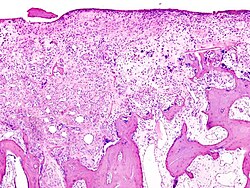

Histopatološke promjene u koljenom zglobu starije pacijentice

Datoteka:Primary osteoarthrosis (1) at knee joint.jpg Datoteka:Primary osteoarthrosis (2) at knee joint.jpg Datoteka:Primary osteoarthrosis (3) at knee joint.jpg Datoteka:Primary osteoarthrosis (5) at knee joint.jpg